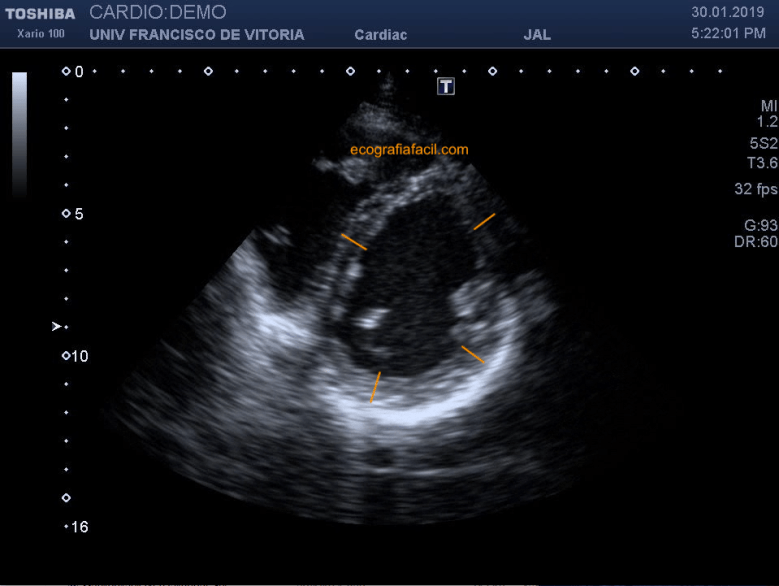

Después, cuando estemos en la mitad del VI podemos parar el movimiento del corazón (¡por favor, sólo el clip adquirido, no el corazón real del paciente!) en el momento final de la diástole; o sea, cuando las paredes son más delgadas, para hacer mediciones de los espesores parietales del VI (figura 16).

Then, when we are in the middle of the LV, we can stop the movement of the heart (please, only the acquired clip, not the real heart of the patient!) At the end of the diastole; that is, when the walls are thinner, to make measurements of the parietal thicknesses of the LV (Figure 16).

No es una medida que hagamos siempre, pero es posible realizarla si no vimos bien las paredes en el eje largo anterior.

It is not a measure that we always do, but it is possible to do it if we did not see the walls in the previous long axis